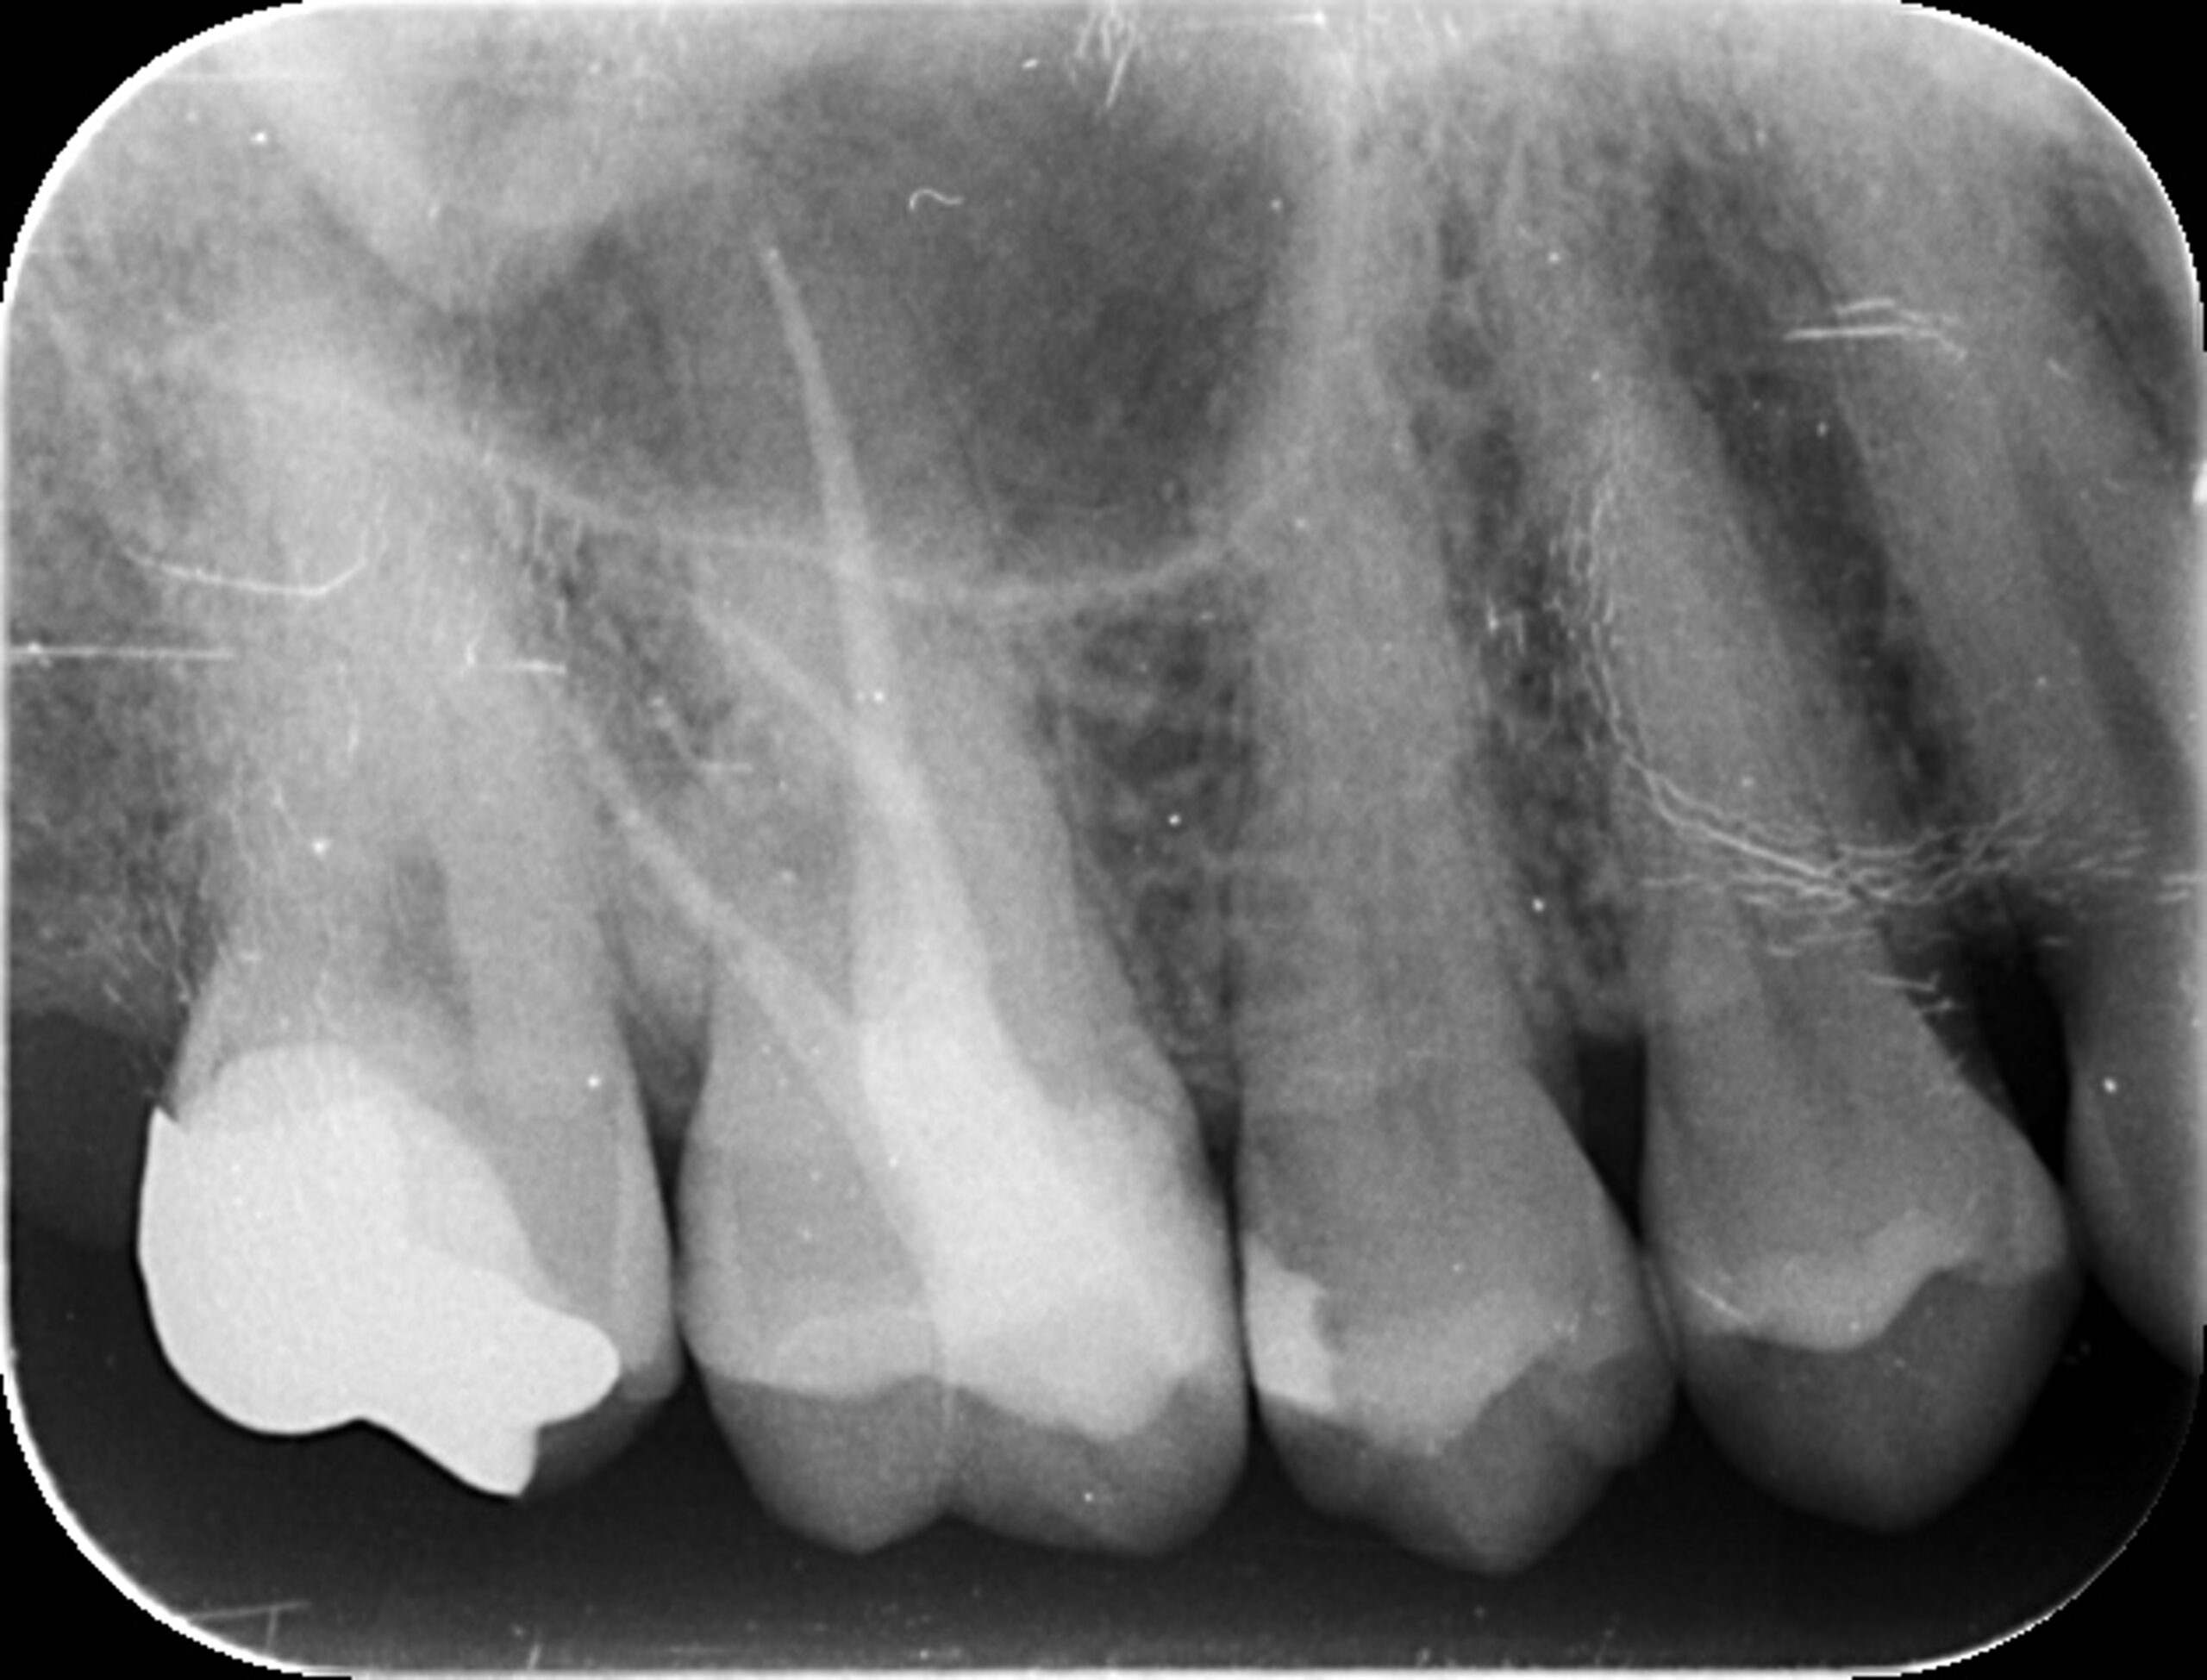

症例1:パーフォレーションリペア症例

(歯の中に大きな穴が空いてしまっているのを埋めて再生を促す治療)

歯に穴が空いていて骨に炎症がある状態 |

CTでも歯の周囲に骨がないのが分かる。 |

人為的根穿孔を起こした部分に感染を起こしており、歯周ポケットが9㎜ありました。 ラバーダム防湿とマイクロスコープを使用して丁寧に治療を行いました。 殺菌性があり歯を補強することのできるMTAという根管充填材料を使用して、歯周ポケットは2㎜に改善しました。 |